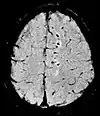

| Diffusion weighted (DWI) | Conventional | DWI | Measure of Brownian motion of water molecules[24]. | High signal within minutes of cerebral infarction (pictured)[25]. | ![]() |